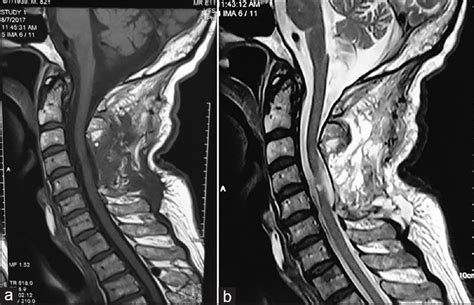

Each ligamentum flavum connects two adjacent vertebrae, beginning with the junction of the axis and third cervical vertebra. Ligamentum flavum consists of collagen fiber namely of elastin. Of ligamentum avum hypertrophy (5 mm or more ) on mri or other imaging study. Ligamenta flava (ligamentum flavum) is thin, broad, and long in the cervical spine or the neck. Sagittal t2 (a) and axial t2 (b) weighted images: Ossification of the ligamentum flavum(olf) is a rare entity seen in the united states. Ct myelography and mri showed facet hypertrophy with ossification of the ligamentum flavum at. They connect the laminae of adjacent vertebrae, all the way from the second vertebra, axis, to the first segment of the sacrum.

Measurements of ligamentum flavum thickening at lumbar spine using mri. As we age, the ligament loses elastin. The ligamentum flavum is considered to be one of the important causes of radiculopathy in lumbar. They connect the laminae of adjacent vertebrae, all the way from the second vertebra, axis, to the first segment of the sacrum. Ossification of the ligamentum flavum(olf) is a rare entity seen in the united states. Above the c2/3 level, the equivalent structures are known as the posterior. Magnetic resonance imaging of 28 patients with radiological and/or histopathologically proved ossification of the ligamentum flavum (olf) was reviewed. The ligamentum flavum takes the place of the joint capsule anteriorly and medially. Ligamentum flavum consists of collagen fiber namely of elastin. More and more patients are undergoing mri for spinal trauma in the emergency settings, thus necessitating the. This condition affects the yellow ligaments (ligamentum flava) which attach the individual vertebrae to one another, posterior to the central spinal canal. T2 sagittal (a), t1 axial (b), t1 with. Nula and a dilator were placed through a small incision over the guide wire, following which the dilator and the guide wire were removed leaving the cannula in place.

This condition is quite common for people who have chronic back pain. Ligamentum flavum hypertrophy might cause a spinal ligament on the posterior side of the central canal to impinge on the spinal cord. Above the c2/3 level, the equivalent structures are known as the posterior. Ct has largely been replaced by mr imaging for the diagnosis of ligamentum flavum, pedicle, transverse process, or vertebral body. Magnetic resonance imaging of 28 patients with radiological and/or histopathologically proved ossification of the ligamentum flavum (olf) was reviewed. They connect the laminae of adjacent vertebrae, all the way from the second vertebra, axis, to the first segment of the sacrum. T2 sagittal (a), t1 axial (b), t1 with. Nula and a dilator were placed through a small incision over the guide wire, following which the dilator and the guide wire were removed leaving the cannula in place.

Nula and a dilator were placed through a small incision over the guide wire, following which the dilator and the guide wire were removed leaving the cannula in place. This condition is quite common for people who have chronic back pain. The elastin pulls the ligament out of the canal when the spine is extended. Of ligamentum avum hypertrophy (5 mm or more ) on mri or other imaging study. Ct and mri characteristics of ossification of the ligamenta flava in the thoracic spine. They connect the laminae of adjacent vertebrae, all the way from the second vertebra, axis, to the first segment of the sacrum. (c) there was no significant. The ligamentum flavum is considered to be one of the important causes of radiculopathy in lumbar. This ligament connects under the facet joints to create a small curtain over the posterior openings between the vertebrae. Ligamentum flavum hypertrophy might cause a spinal ligament on the posterior side of the central canal to impinge on the spinal cord. Magnetic resonance imaging (mri) of the cervical spine. The magnetic resonance imaging (mri) of the lumbar spine revealed a mass, measuring about 2.6x1.3x1.2cm in size, at a location posterior to (b) axial view showed that the mass was within the ligamentum flavum. Ligamentum flavum by dynamic disc designs corp.